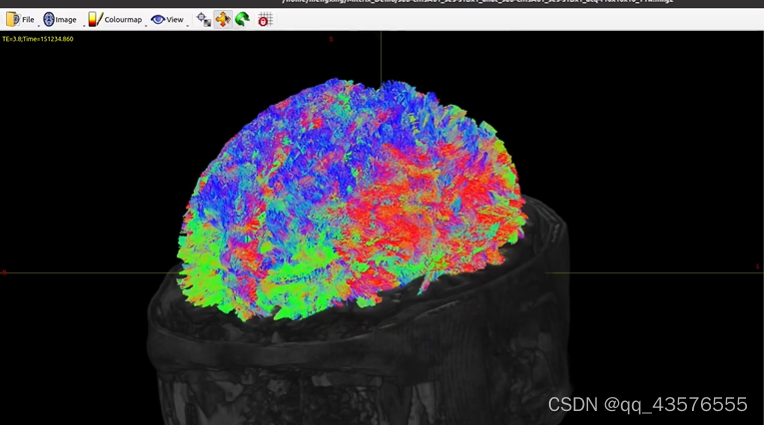

(zf) hzhb@hzhb:~/Fengz/demo$ tckgen -algo iFOD2 -act sub-cIIIsA01/5ttseg.mif -backtrack -crop_at_gmwmi -cutoff 0.05 -angle 45 -minlength 20 -maxlength 200 -seed_image dwi_wmMask.mif -select 200k dwi_wmCsd.mif fibs_200k_angle45_maxlen200_act.tck

tckgen: [100%] 367099 seeds, 259465 streamlines, 200000 selected将得到的追踪像 .tck文件和结构像T1w放在mrview中打开,选择Tractography选项,就得到了对比图如下,可以选择不同的切面

基于兴趣区的追踪与之类似,改变某些参数即可,下图为视觉纤维束